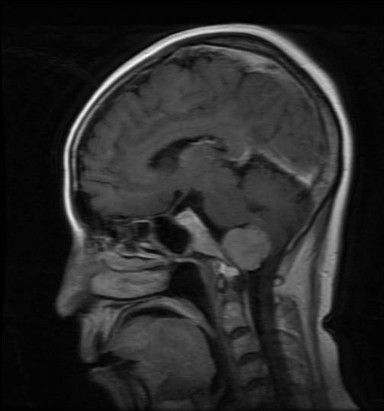

病例一:张**。女性,52岁。查体发现枕骨大孔区占位入院。临床诊断:枕骨大孔区腹侧脑膜瘤。术式:远外侧入路。术后病理脑膜瘤。

术前